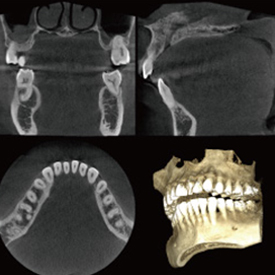

精度が高い診査・診断&安心・安全な治療歯科用CT- Computer Tomograghy -

CTとはComputer Tomograghyの略で、日本語ではコンピューター断層撮影と訳されます。

これは、X線とコンピューターによって、歯や骨の位置や形態などを3D画像で立体的に撮影するための医療機器です。

血管や神経の位置を立体的に把握し、骨量、骨密度を正確に確認できるため、インプラント治療の際にはCTによる診査・診断が必須となっています。

また、CTは、インプラント治療だけでなく、全ての歯科治療の精度向上に役立ちます。

歯槽骨の状態や根管の形態等をより正確に把握することができるため、埋伏歯抜歯、矯正治療、根管治療、歯周病治療など、さまざまな治療において、より正確な診査・診断、治療の高度化が期待できます。

多くの歯科医院では、CTを撮影するために外部のスキャニングセンターへ撮影に出向く必要がありますが、当クリニックでは院内にCTを設置しているため、レントゲンと同じように院内で撮影し、即座に診ることができます。